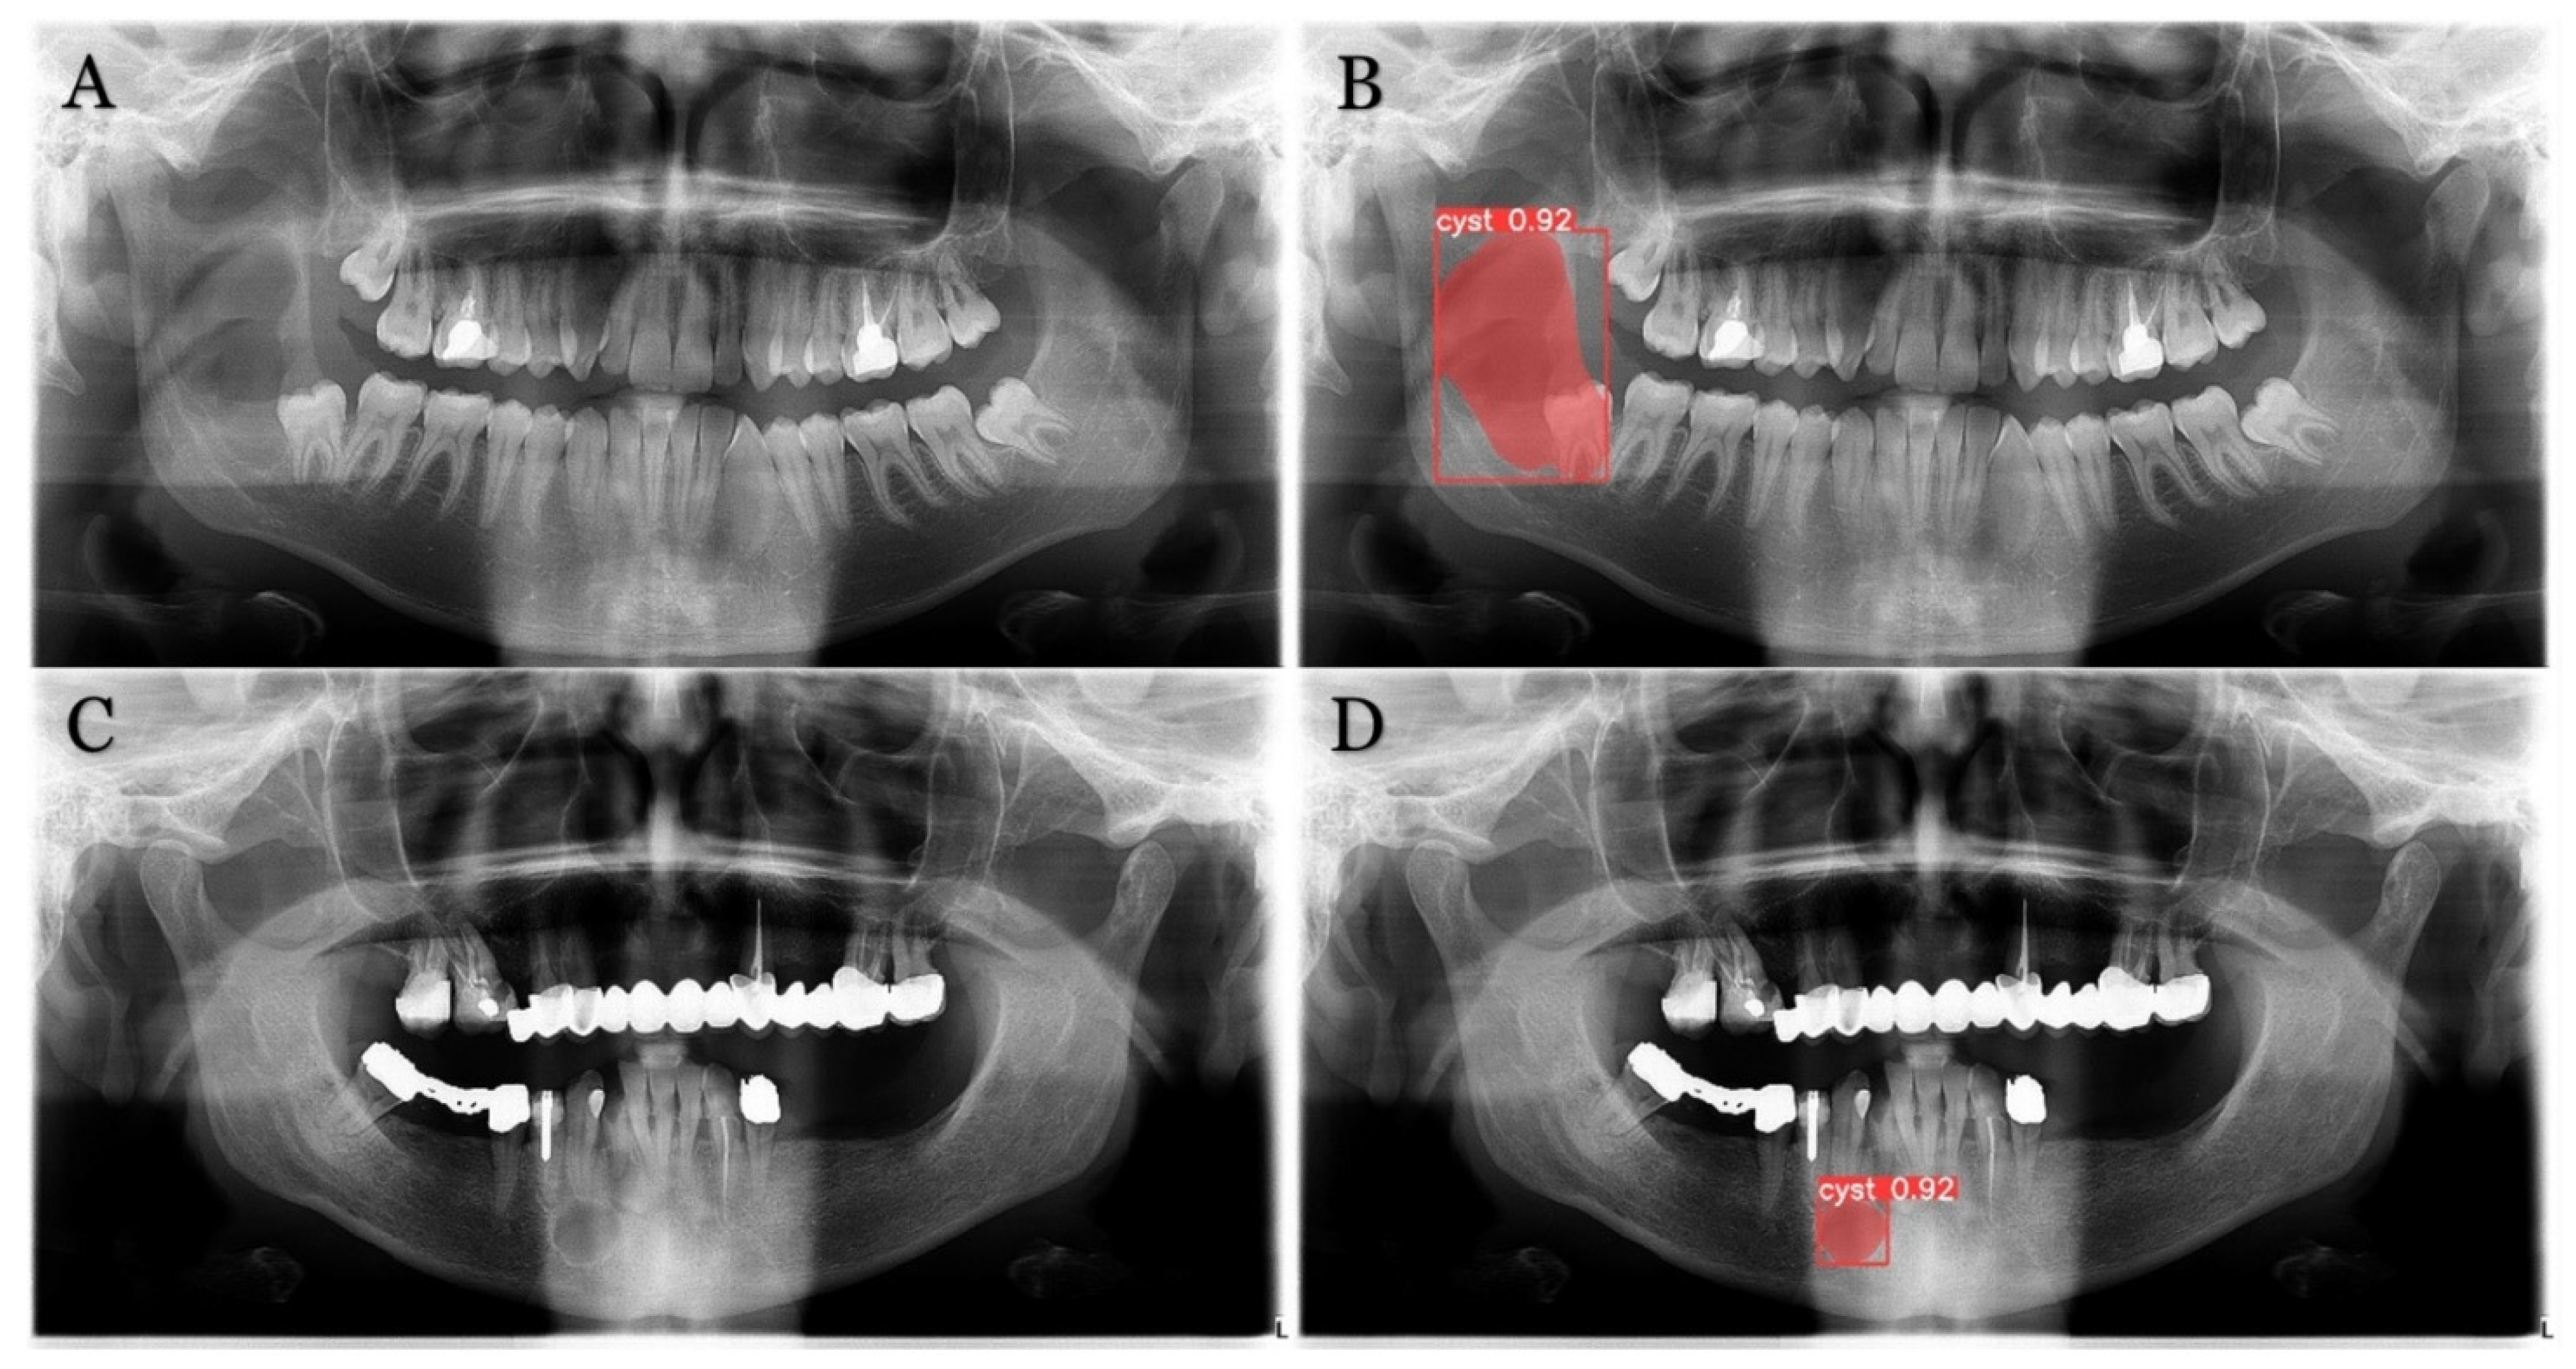

The inclusion criteria were the presence of a radiolucent lesion in the lower jaw and histopathologic verification of the diagnosis. These radiographs included 226 radiolucent lesions (Table 1). Radicular cyst, ameloblastoma, odontogenic keratocyst (OKC), dentigerous cyst and residual cyst were the included diagnoses (Figure 1).

Figure 1. Examples of the included lesions. (A) Radicular cyst, (B) Ameloblastoma, (C) Odontogenic keratocyst (OKC), (D) Dentigerous cyst, (E) Residual cyst.